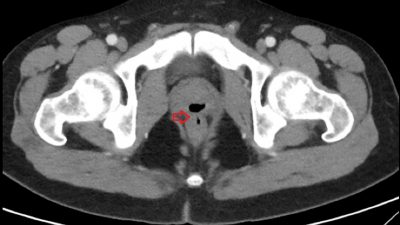

Screenshot hasil CT scan munculnya lubang tak lazim di pasien asal AS yang membuatnya ejakulasi lewat pantat.

Awalnya, lelaki itu mengeluhkan rasa nyeri di buah zakarnya. Ketika menjalani proses CT Scan, ketahuan lah kalau ada lubang yang tak lazim, menghubungkan kawasan prostat ke rektum. Alhasil semen dan urin, yang seharusnya terpisah dari rektum, justru mengalir semua ke lubang pantatnya.

Lubang macam itu, biasa disebut fistula oleh para dokter, bukan hal bisa secara alamiah muncul di organ manusia. Mereka kemudian menyelidiki, apakah dia pernah menjalani operasi di area prostat. Kemudian, terungkaplah dua tahun sebelum mengalami ejakulasi lewat anus, lelaki malang ini sempat menjalani operasi kateter, yakni pemasangan tabung kecil yang fleksibel dan biasa digunakan mengosongkan kandung kemih.